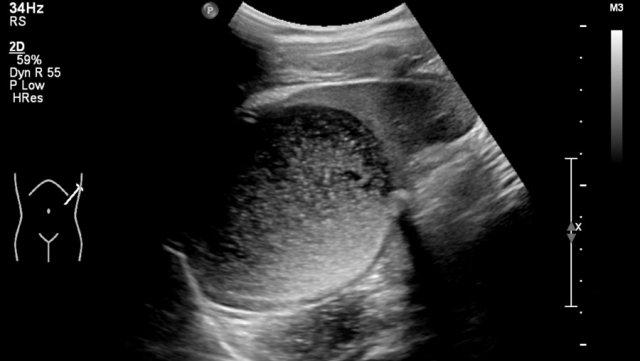

Hình ảnh của một bé trai 1 tháng tuổi được phát hiện MCKD trên siêu âm trước sinh.

Có thể thấy một ít mô thận và nhiều nang lớn.

Trên xạ hình thận với Tc-99-DMSA, không ghi nhận sự hấp thu ở phía bên trái.

Hình ảnh này phù hợp với bệnh thận đa nang loạn sản (MCKD).